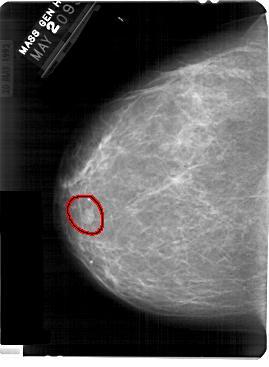

A_1369_1.RIGHT_CC

RIGHT_CC LINES 5491 PIXELS_PER_LINE 3766 BITS_PER_PIXEL 12 RESOLUTION 43.5 NON_OVERLAY

FILE: A_1369_1.LEFT_MLO.OVERLAY

TOTAL_ABNORMALITIES 1

ABNORMALITY 1

LESION_TYPE MASS SHAPE OVAL MARGINS CIRCUMSCRIBED

ASSESSMENT 4

SUBTLETY 5

PATHOLOGY BENIGN

TOTAL_OUTLINES 1

BOUNDARY